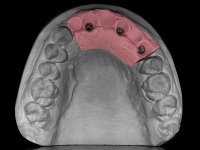

O paciente foi observado conjuntamente e a dúvida que surgiu de imediato foi se seria possível com a regeneração óssea a efectuar poder ser reabilitada naturalmente a zona das papilas interdentárias. Nesse sentido foi feito um enceramento de diagnóstico que contemplaria as duas hipóteses, utilizando ou não a cerâmica gengival. A confecção desse enceramento foi fundamental para expor ao paciente a dificuldade da reabilitação. O wax-up deu origem a um mock-up que foi aprovado pelo paciente e que simultaneamente serviu de guia imagiológica. O caso foi planificado cirurgicamente e realizada uma guia cirúrgica com que foram colocados os implantes. Após 10 semanas foi feita a 1ª impressão para confecção da ponte provisória. Foram criados os primeiros perfis de emergência na gengiva artificial e foi digitalizado o modelo. Por processo de CAD-CAM foi confeccionada uma ponte provisória aparafusada baseada no enceramento de diagnóstico. A ponte trabalhou durante 8 semanas os tecidos moles que foram fielmente copiados numa impressão com técnica de moldeira aberta. Os transferes foram individualizados com resina composta para copiarem fielmente os perfis de emergência criados pela ponte provisória. Confeccionado o modelo de trabalho definitivo, foi realizada uma infra-estrutura em zircónio seguindo a orientação do enceramento de diagnóstico. O assentamento da infra-estrutura foi testado em boca e simultaneamente foi novamente impressionados os tecidos moles com um silicone fluido. Nessa consulta foi feito o levantamento da cor. Os dentes 13 e 23 apresentavam uma saturação anormalmente forte que resolvemos não valorizar, optando por privilegiar a relação com o sector antero-inferior. Foi realizada uma nova gengiva artificial com a impressão que acompanhou a impressão de arrasto com a infra-estrutura. Após a colocação da cerâmica na infra-estrutura foram coladas as meso-estruturas. O trabalho final foi aparafusado lentamente permitindo a adaptação dos tecidos moles.